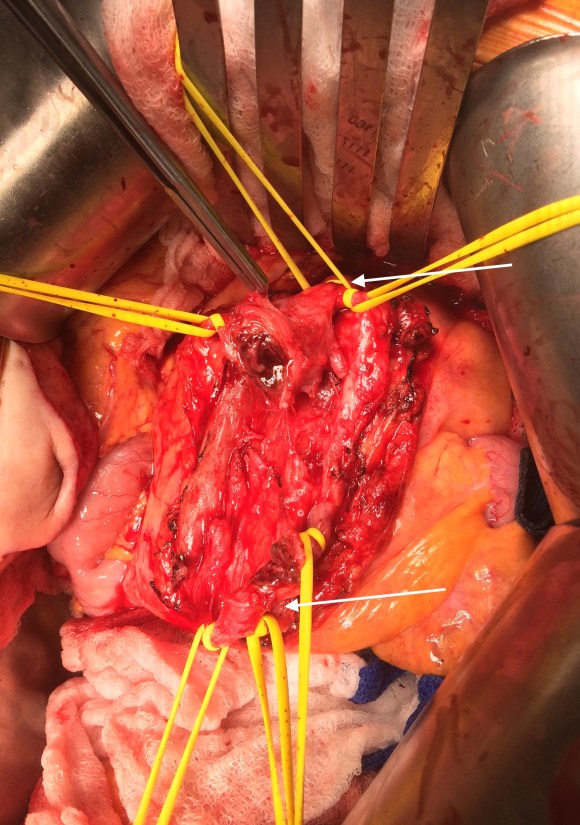

After being satisfied with the completion, I removed the sheaths and explored the abdomen finding this segment of infarcted small bowel (next image).

There was no question in my mind that there would be some dead bowel based on the time course described by the patient. Despite my excitement about calling for GIA staplers -I am general surgery boarded- I called in the general surgeons for their help in resecting and anastomosing this segment of bowel. They would be the ones taking the patient back for any second look laparotomy, although in this patient, I determined that there would likely be no need. After the anastomosis was completed, I did a Wood’s Lamp examination (pictured), which is accomplished with a black light after giving the patient an ampule or two of Fluorescein.

The bowel had a splotchy fluorescence pattern which is typical of ischemia-reperfusion. This is where you have to ask the anesthesiologist and any critical care specialist who follows -no pressors please! Edema won’t kill an anastomosis as badly as ischemia will, and the gut is as sensitive to norepinephrine as are the toes. Workup in the hospital including echocardiography and CTA of the entire aorta failed to reveal a proximal source or cardiac shunts or thrombus. The patient recovered and has recently followed up, eating well, and tolerating his anticoagulation which he will be on for life.